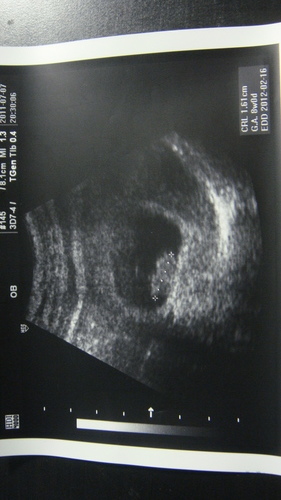

北鼻0.6公分大~~比我的小指指甲尖還小耶!

(黑黑的那圈是胚囊~醫生拉的那條線那裏才是胚胎喔)

不過才一個禮拜~北鼻已經長了4倍大囉!

不像上次需要很仔細看~這次已經看出一個很明顯的肉球了XD

依照書上說~這個時候已經有小手小腳了哩(不過我是看不出來)